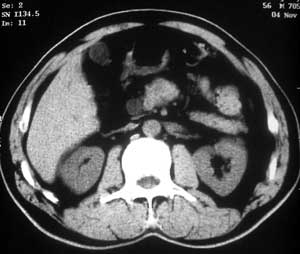

患者,男,57岁,梗阻性黄疸10余天。

这个病例胰头无明显增大,胆总管扩张明显而肝内胆管扩张更不明显,病程较短,

注意到十二指肠乳头明显突出,但尚光滑。分析以下可能性:

1、十二指肠乳头本身的病变,如乳头炎症;

2、急性乳头水肿,胆总管下端结石排石后乳头水肿;

3、壶腹部胆总管下端肿瘤累及十二指肠乳头。

十二指肠乳头粘膜慢性非特异性炎症